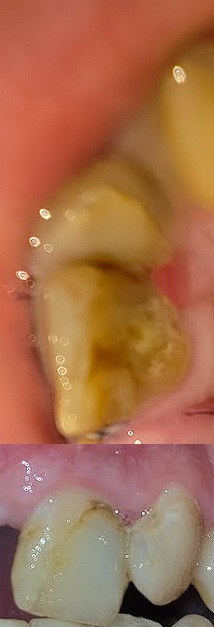

960x1280

>>1657604

Вот даже кусок старого рентгена остался трёхлетней давности